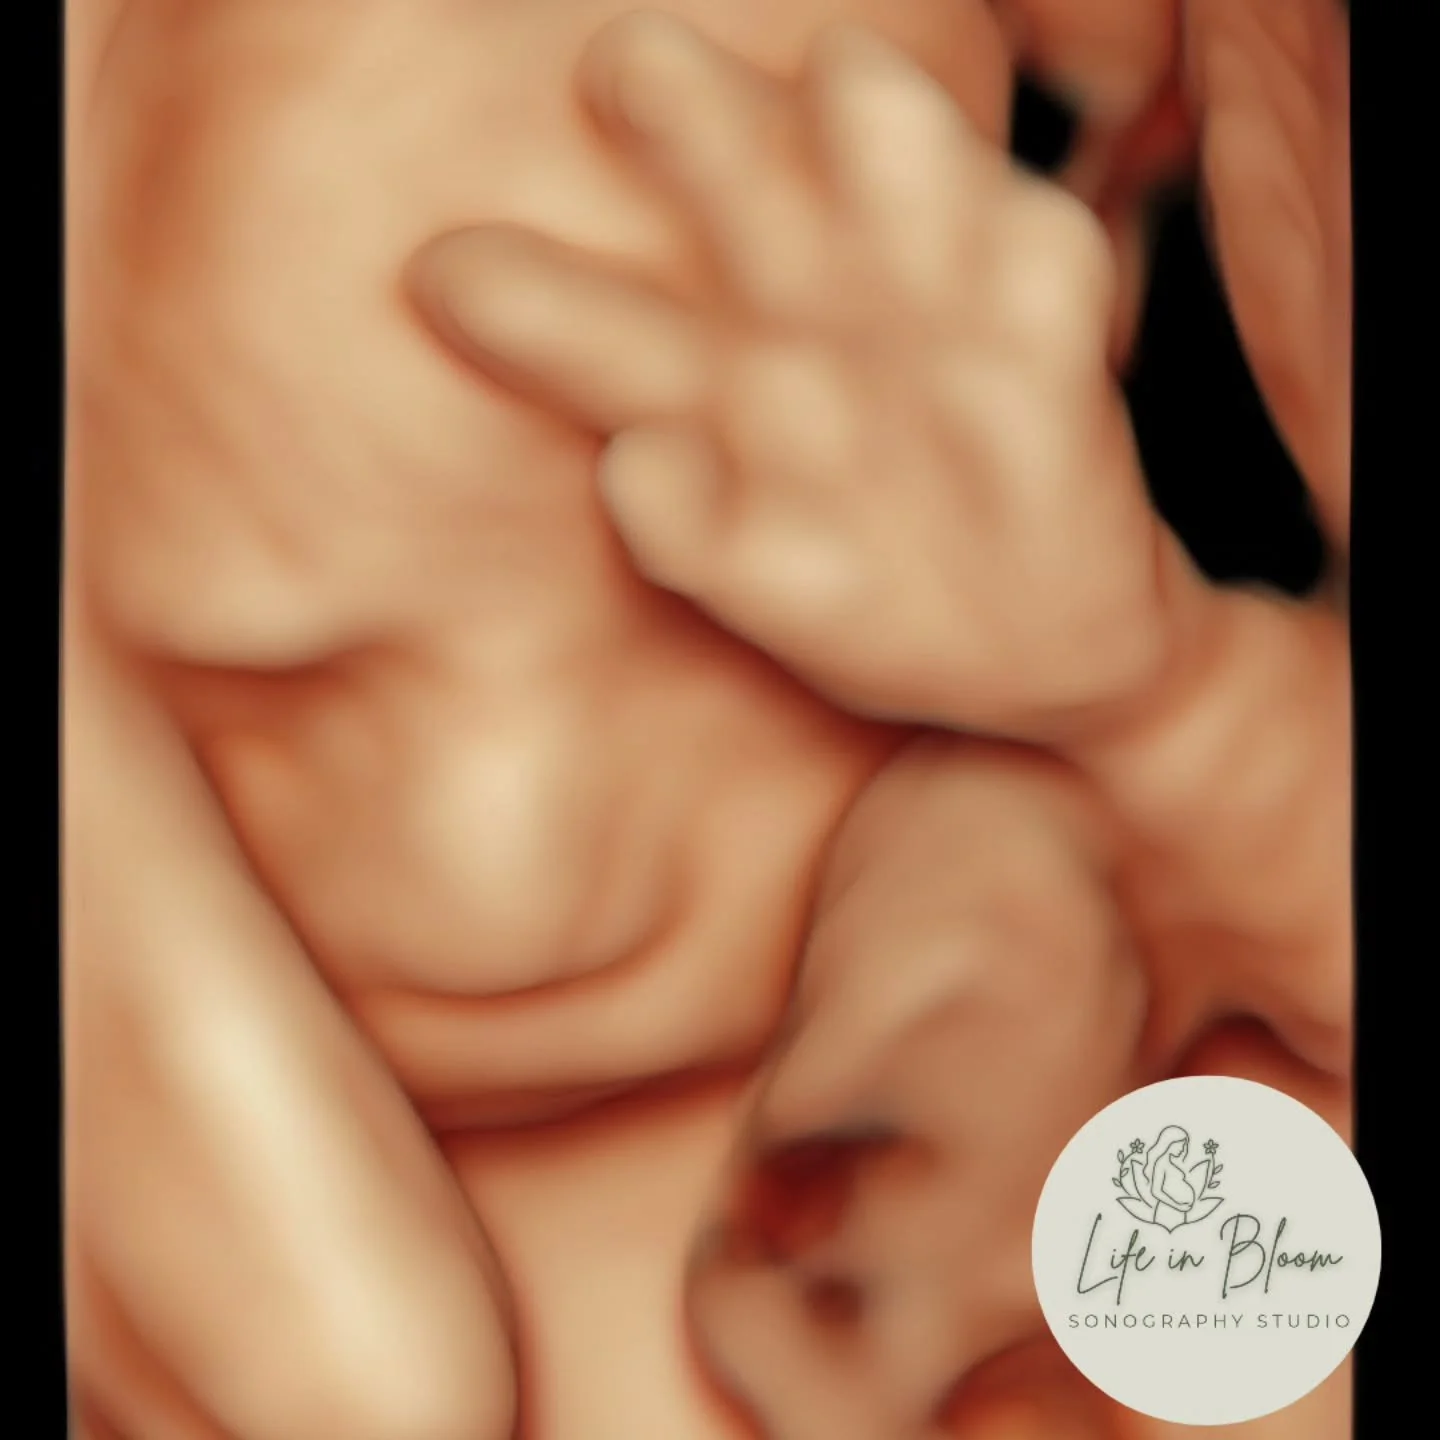

Our state of the art technology allows us to see your baby in a whole different way! With HD Live imaging, we can watch your baby wiggle, smile and yawn all in real time!